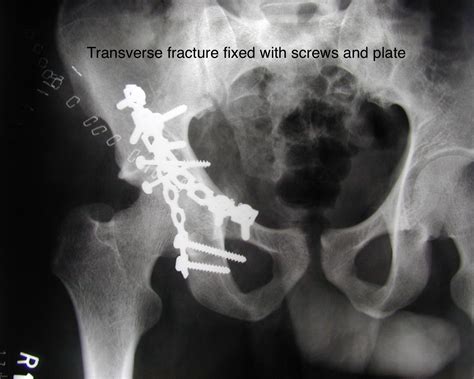

• transverse process fracture radiology

• transverse process fracture radiopaedia